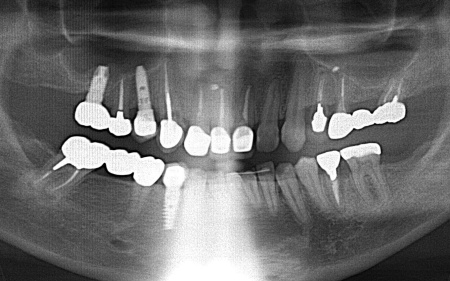

| 診断 | 拝見したところ、左上奥歯(第1小臼歯)は歯の上の部分である歯冠が折れ、歯根のみ残っている状態でした。 また、左下奥歯(第2小臼歯)には被せ物が装着されています。 レントゲン撮影をして痛みの原因を詳しく検査したところ、左上下奥歯の歯根が割れており、その影響で痛みが出ていると考えられました。 歯根が割れた歯は温存が難しく、このまま放置すると炎症が広がって周囲の歯に悪影響を及ぼすおそれがあるため、抜歯せざるを得ない場合があります。 以上のことから、温存が難しいと判明している左上奥歯は抜き、左下奥歯は被せ物を取り外して内部を確認したうえで、適切な処置を行うことが望ましいと診断しました。 |

| 行ったご提案・治療内容 | 診断結果をお伝えし、患者様の了承を得たうえで左下奥歯の被せ物を外したところ、レントゲン検査での診断どおり、歯根が割れていることが確認できました。 そのため、患者様には左上下奥歯とも温存が難しい旨を説明し、抜歯に同意いただきました。 患者様は、以前当院で人工歯根を顎の骨に埋入して歯を装着するインプラント治療を受けていたため、今回も左上下奥歯ともインプラント治療を希望されています。 メリット デメリット 改めてメリットとデメリットをしっかりお伝えしたところ、インプラント治療に対する不安はないとのことで、治療に同意いただきました。 まず、左上下奥歯を慎重に抜きます。 インプラント手術後は経過観察を行い、インプラントが顎の骨に結合したことを確認したら、インプラント上部に取り付ける人工歯を作製するために精密な型取りを実施します。 後日、完成した人工歯をインプラントに装着し、使用感や見た目に問題がないことを確認して、治療を終了しました。 |

| 治療期間 | 約4ヶ月 |

| 費用 | 約840,000円 | 治療のリスク | ・外科手術のため、術後に痛みや腫れ、違和感を伴います ・メンテナンスを怠ったり、喫煙したりすると、お口の中に大きな悪影響を及ぼし、インプラント周囲炎等にかかる可能性があります ・糖尿病、肝硬変、心臓病などの持病をお持ちの場合、インプラント治療ができない可能性があります ・高血圧、貧血・不整脈などの持病をお持ちの場合、インプラント治療後に治癒不全を招く可能性があります ・装着に際し、天然歯を削る場合があります ・硬い素材の場合、他の天然歯を傷つけることがあります |